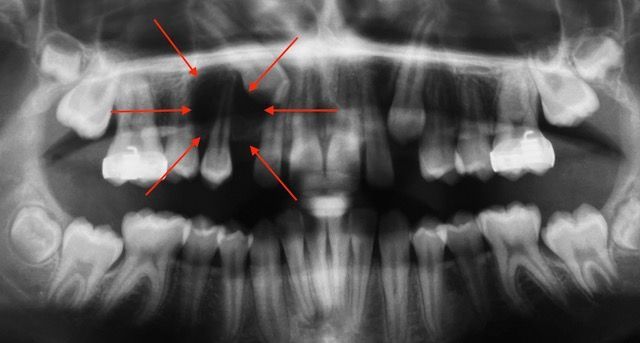

Agganciamento dei canini superiori inclusi

Canini superiori inclusi

Agganciamento canini superiori inclusi

Entrambi i canini sono stati agganciati chirurgicamente per l'allineamento